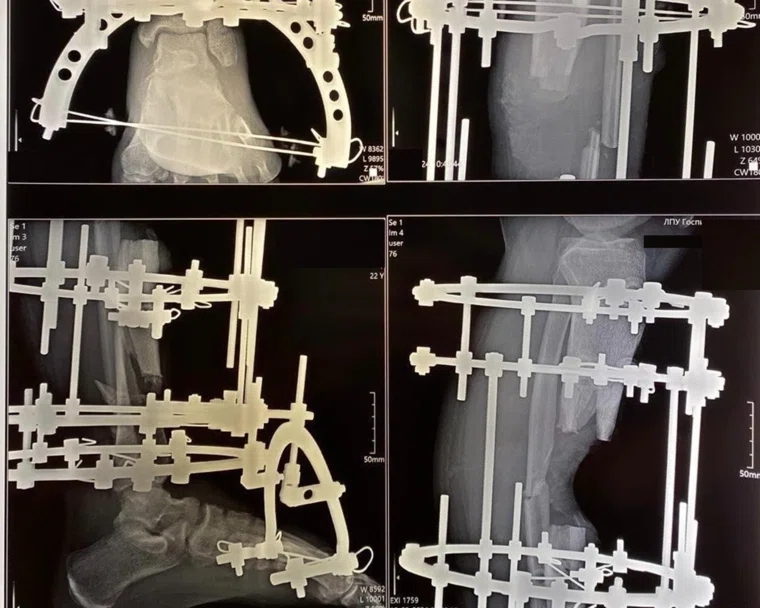

Ключевым инструментом лечения стал аппарат Илизарова — уникальное устройство, позволяющее фиксировать и постепенно сращивать сложные переломы, устранять дефекты кости, восстанавливать длину и ось конечности. Врачи поэтапно боролись с инфекцией, устраняли последствия остеомиелита, фиксировали отломки и стимулировали регенерацию костной ткани.

Лечение включало несколько операций, длительное ношение аппарата Илизарова, физиотерапию и постоянный медицинский контроль. Каждый этап требовал терпения и выдержки от пациента, а также слаженной работы врачей, медсестер и реабилитологов.

Через полтора года после поступления в госпиталь мужчина смог встать на обе ноги. Полностью восстановлена опорная функция конечности, устранен дефект кости, ликвидирована инфекция. Пациенту удалось вернуться к нормальной жизни, чего еще недавно никто не мог гарантировать.